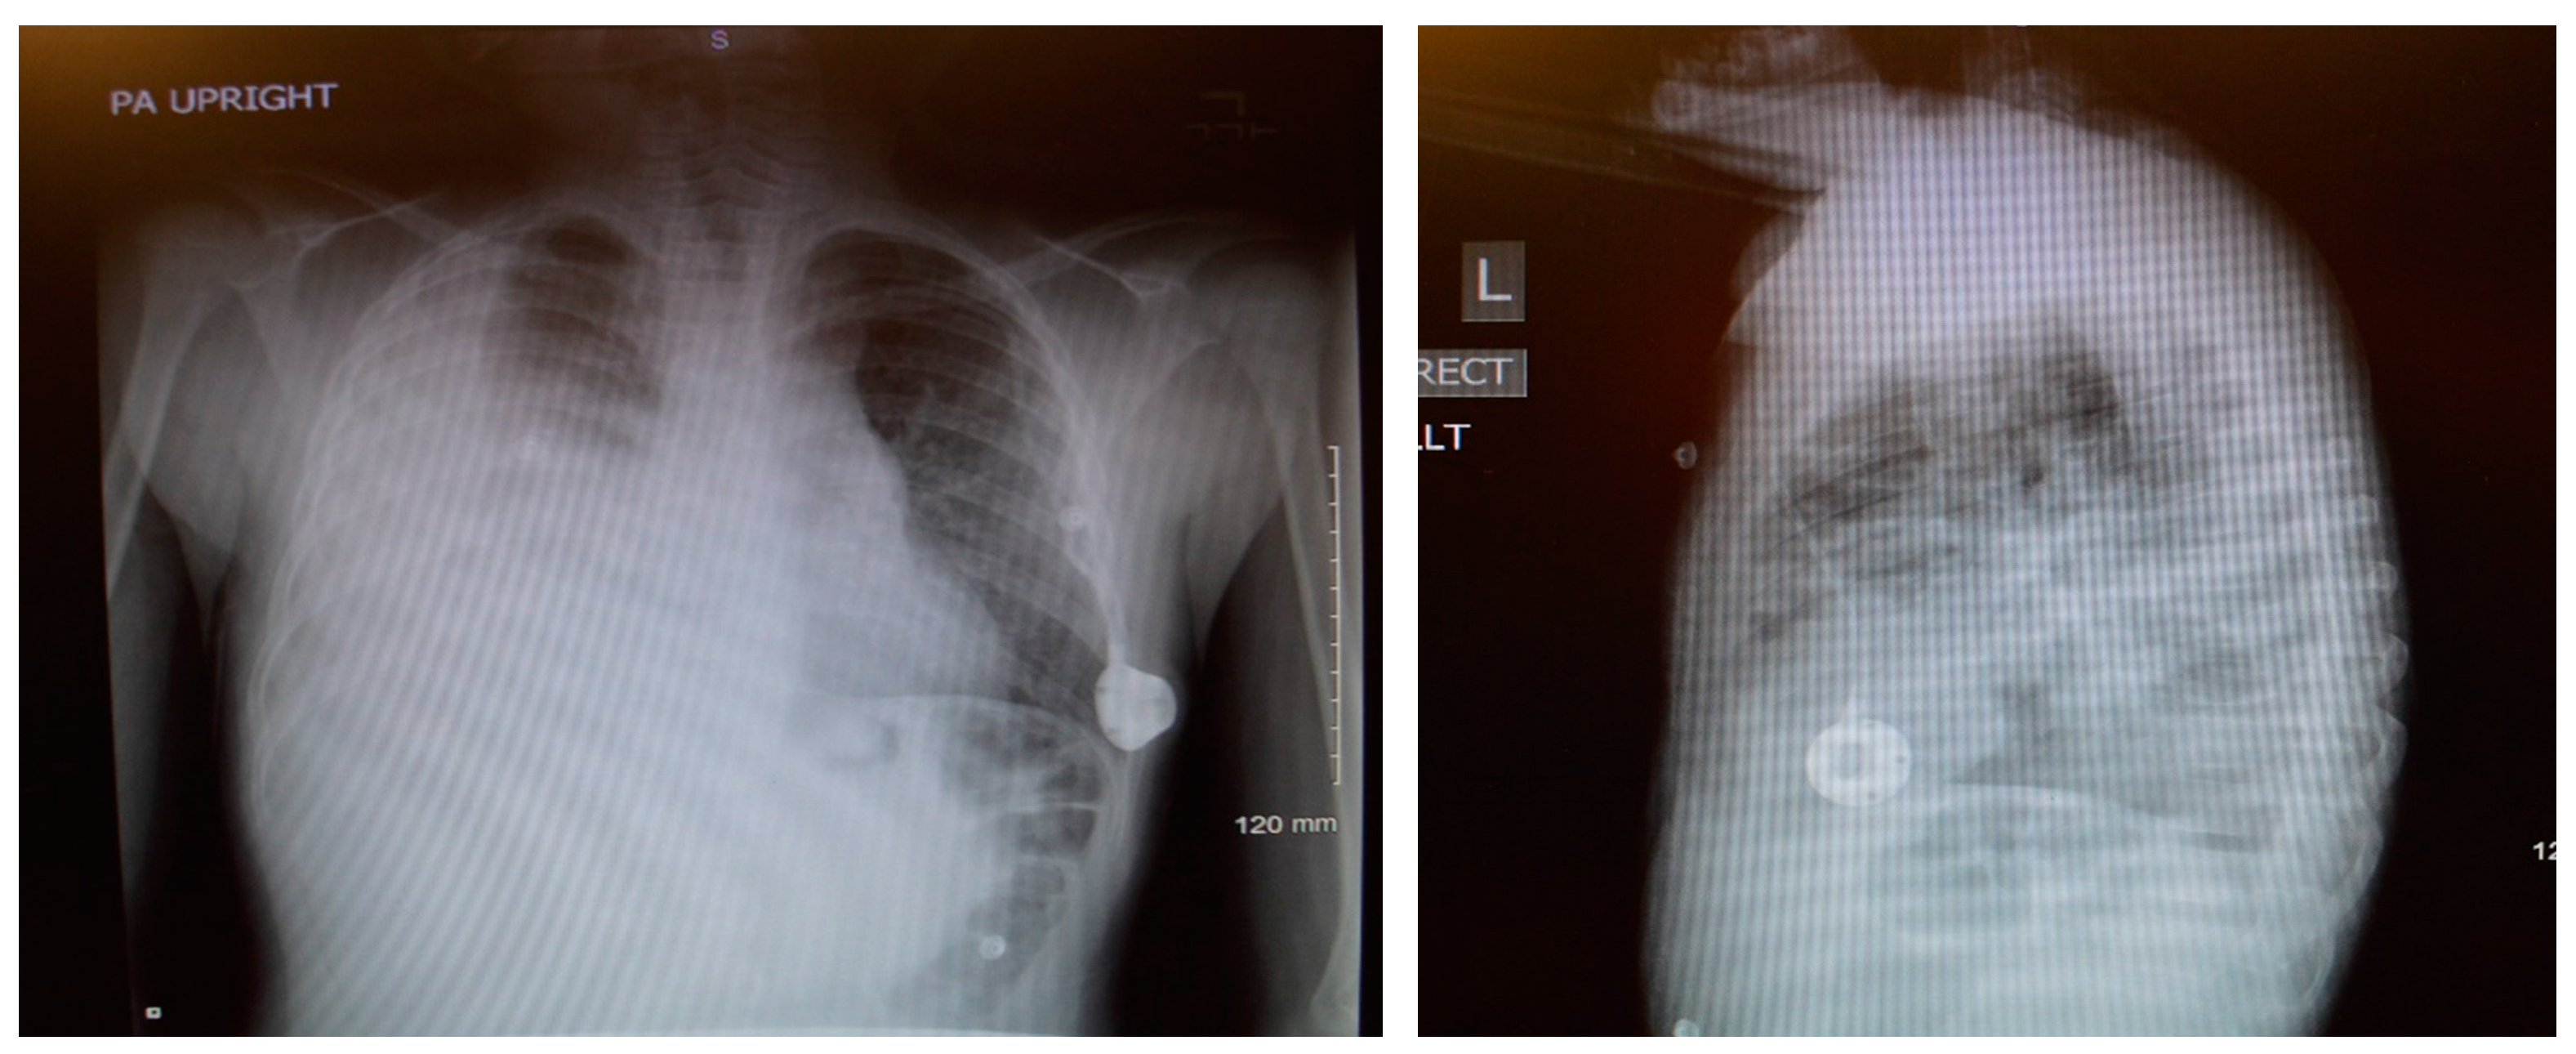

An 8-year-old male patient with a history of SCD maintained on long term erythrocytapheresis (LTE) for primary prevention of stroke due to a history of increased transcranial Doppler velocities presented with several days of fatigue, decreased oral intake, chest pain, and palpitations. Imaging studies showed a large right-sided pleural effusion with underlying atelectasis or consolidation (Figure 1). A chest tube was inserted for drainage of the pleural fluid, which continued to have significant output for several weeks. The pleural fluid had features consistent with chylous effusion, including elevated triglycerides, positive for chylomicrons, and milky appearance.

Figure 1.

Chest X-rays demonstrating undrained right chylothorax.